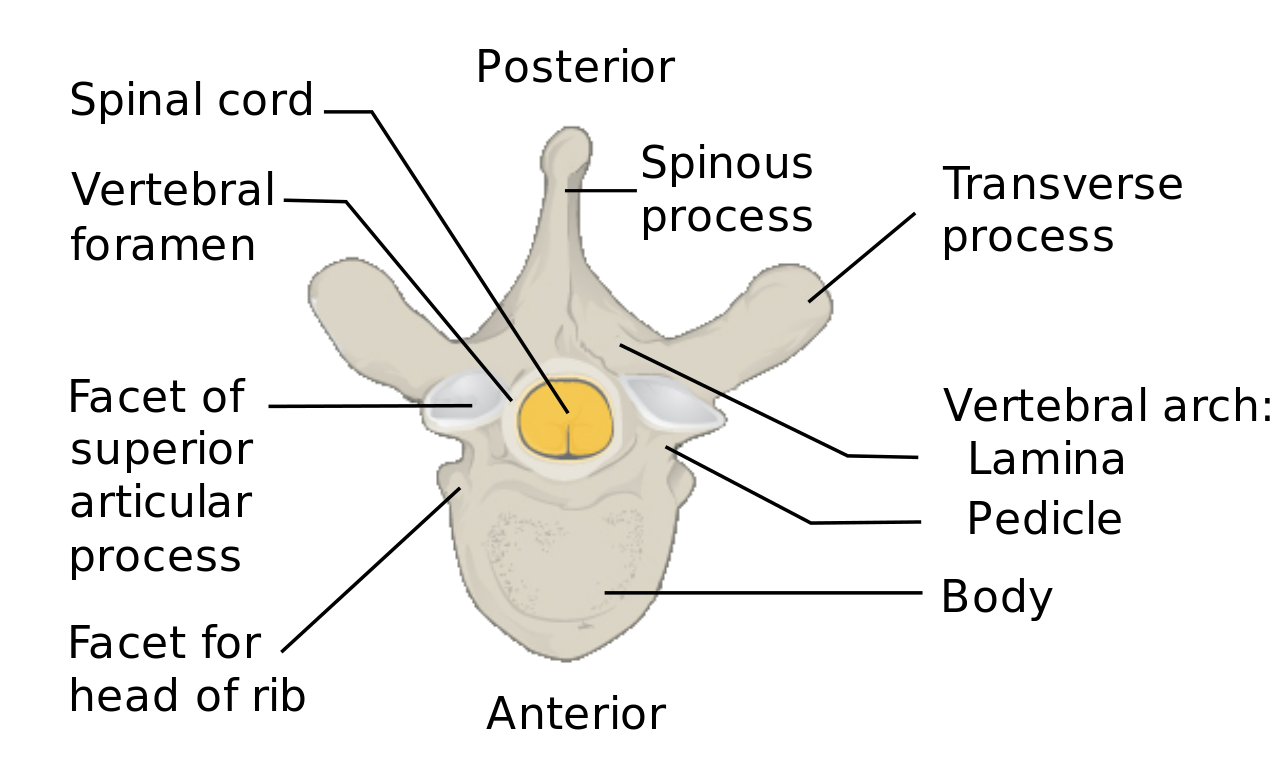

You might not know it, however your reduced back is a complicated framework made up of vertebrae. In order to operate appropriately, these bones need to be secure. However, as we age, the bones in our spinal column begin to press. This can create degenerative changes, which can cause a squeezed nerve. A squeezed nerve can take place all of a sudden or progressively. It might additionally happen due to an injury.